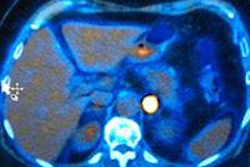

With the arrival of the MRI scanner in the 1980s, courtesy of Paul Lauterbur from the State University of New York at Stony Brook, U.S., and Peter Mansfield from Nottingham University, U.K., the audience was brought up to date with the most significant technologicaladvances in the field. Until relatively recently, most imaging advances have been related to an increase in resolution, but radiology is now entering an exciting era of physiological imaging, Stivaros remarked.

"Using techniques such as diffusion and arterial spin labeling, we can assess cellular packing and brain blood perfusion. Phase contrast MRI allows us to image arterial blood entering the head, venous exiting blood, and CSF flow all noninvasively with no contrast injection," he said.

Specifically highlighting advances in pediatric neuroimaging, Stivaros discussed hydrocephalus as a case in point. Affecting 0.82 people per 1,000, it is not insignificant, and has long been considered simply either as an "obstructive outflow problem or communicating and resultant from poor absorption, but we could never assess this in any shape or form." Now, his research group funded by the NIHR is developing quantitative techniques using phase-contrast MRI in children including a noninvasive method of measuring intracranial pressure.

"Using phase-contrast MRI, blood flow into the brain can be measured," he explained. "And because space is occupied by inflowing blood, then CSF and venous blood exits. The time delay on this allows for the calculation of intracranial pressure."